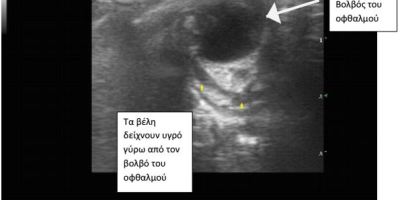

ΥΠΕΡΗΧΟΣ ΟΦΘΑΛΜΩΝ

ΟΠΙΣΘΟΒΟΛΒΙΚΟ ΑΠΟΣΤΗΜΑ